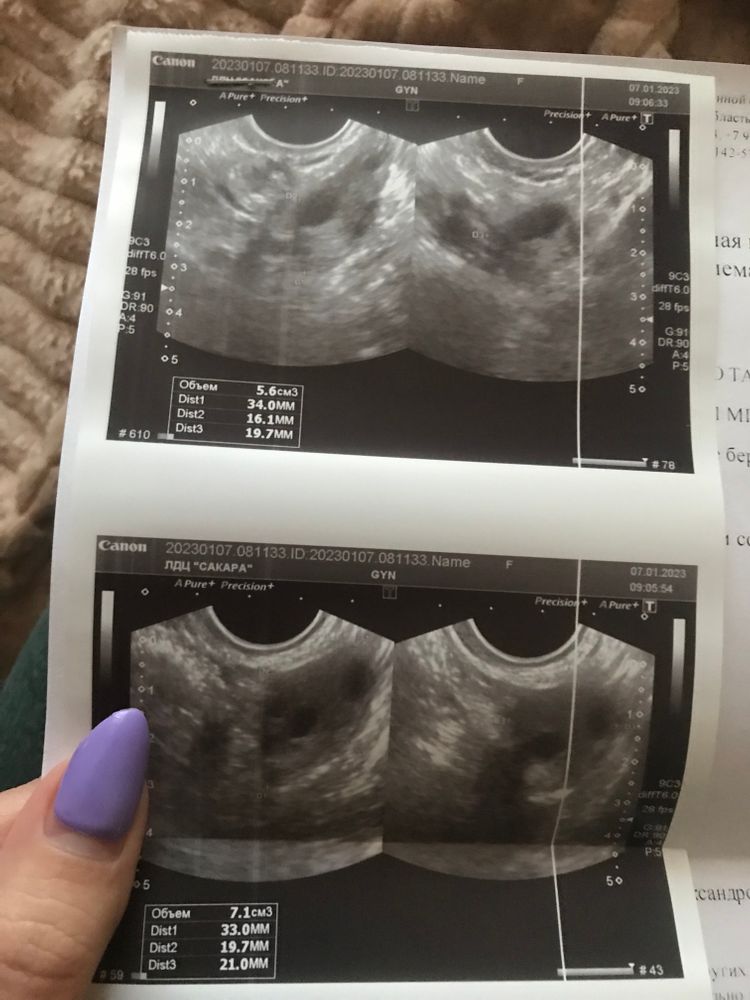

Сикирина Ольга, еще подскажите пожалуйста, нормально, что сегодня 15 день после чистки а хгч так еще не упал до состояния «не беременна»? Плод замер на 9-ой неделе - это же не такой большой срок… тест сегднешний.